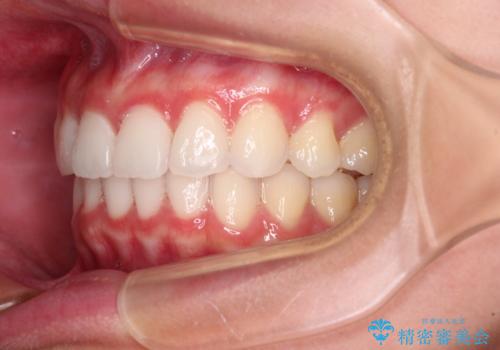

- 前歯2本が飛び出してることを気にして来院された患者様です。

全体的に黄ばんだ歯の色も気になるとのことで、マウスピース矯正により飛び出した前歯を治しつつ、ホームホワイトニングを併用して黄ばみを解消していくこととしました。

歯と歯の間を削ることで、飛び出した前歯が引っ込み、スッキリとした口元となりました。

歯の黄ばみも改善され、明るい歯並びとなりました。